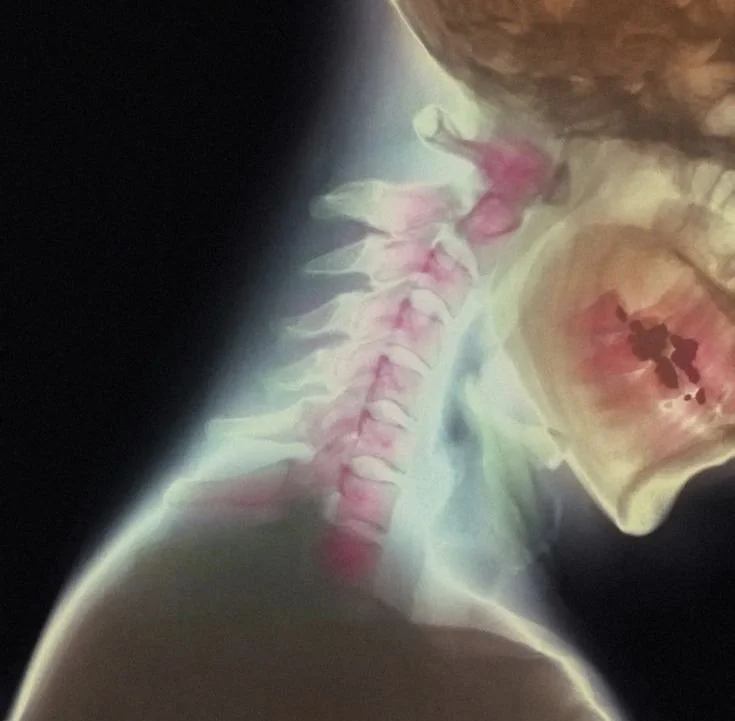

The meeting of heaven and earth in the body occurs at a sacred junction: where your skull meets the top of your spine. Here, two small, pivotal bones form the foundation of this inner axis. They are named, with perfect synchronicity, the Atlas (C1) and the Axis (C2).

The Atlas bone is the first vertebra. It is a ring that cradles the weight of your entire skull, your personal cosmos of thought, perception, and spirit. It is the bone of bearing, the literal Atlas of your anatomy.

Just below it rests the Axis bone, the pivot. It is the turning point that allows your head, your consciousness to rotate, to see from new perspectives, to say “no” and “yes.” Together, they are the **upper cervical spine**, the physical fulcrum of your being.

Yet, this sacred junction is also supremely sensitive and, for most, profoundly blocked. Physical traumas, emotional shocks, and systemic energetic implants often lodge here, creating a **dislocation**, not just in the spine, but in our connection to source. When the Atlas and Axis are misaligned, the Alta Major gateway is stifled. The current is blocked. The sky feels crushingly heavy because the channel is pinched. We live as Atlas straining under a weight we were designed to channel, cut off from the flow that would make us the Axis.

1. Re-aligning the physical Atlas and Axis.